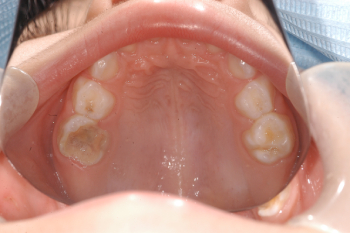

Después: